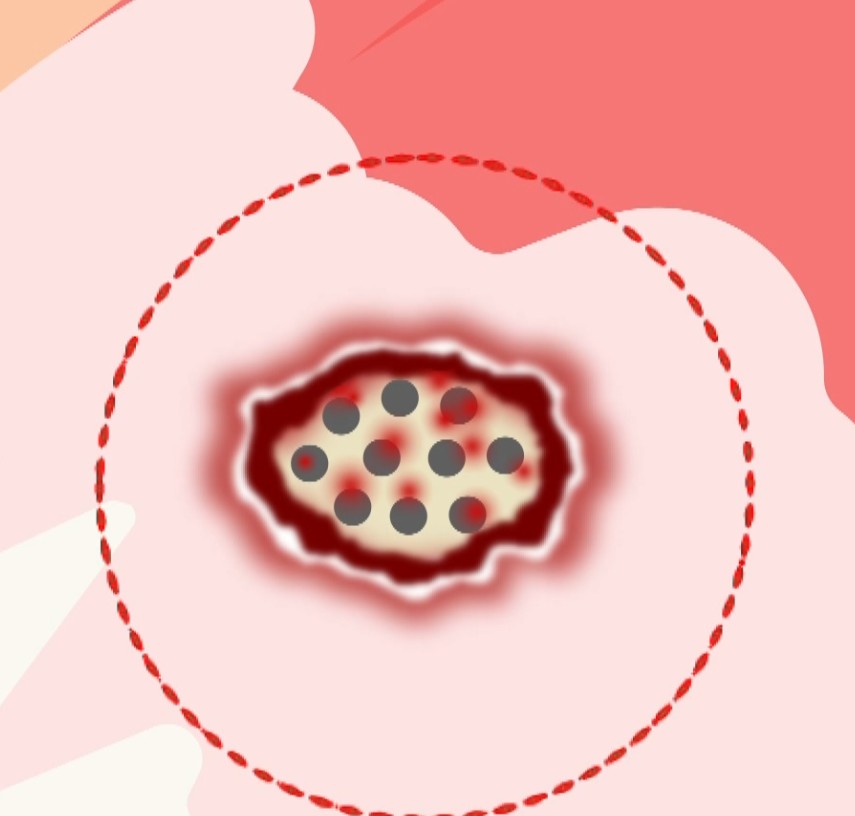

회전근개는 입체적인 구조입니다. 같은 "부분파열"이라도 어느 쪽이 찢어졌는지에 따라 치료법이 완전히 달라집니다.

관절면측(Articular-side) 파열 = 인대 내부가 찢어진 것

회전근개의 아래쪽(관절 쪽)이 손상된 경우입니다.

인대가 뼈에 붙는 부착부(footprint) 부위 손상

혈류 공급이 적어 자연 치유가 어려움

방치 시 전층파열로 진행 위험 높음

점액낭면측(Bursal-side) 파열 = 인대 외부가 찢어진 것

회전근개의 위쪽(점액낭 쪽)이 손상된 경우입니다.

인대의 표면(외부)이 손상됨

관절면측보다 혈류 공급이 좋음

적절한 치료 시 재생 가능성 높음